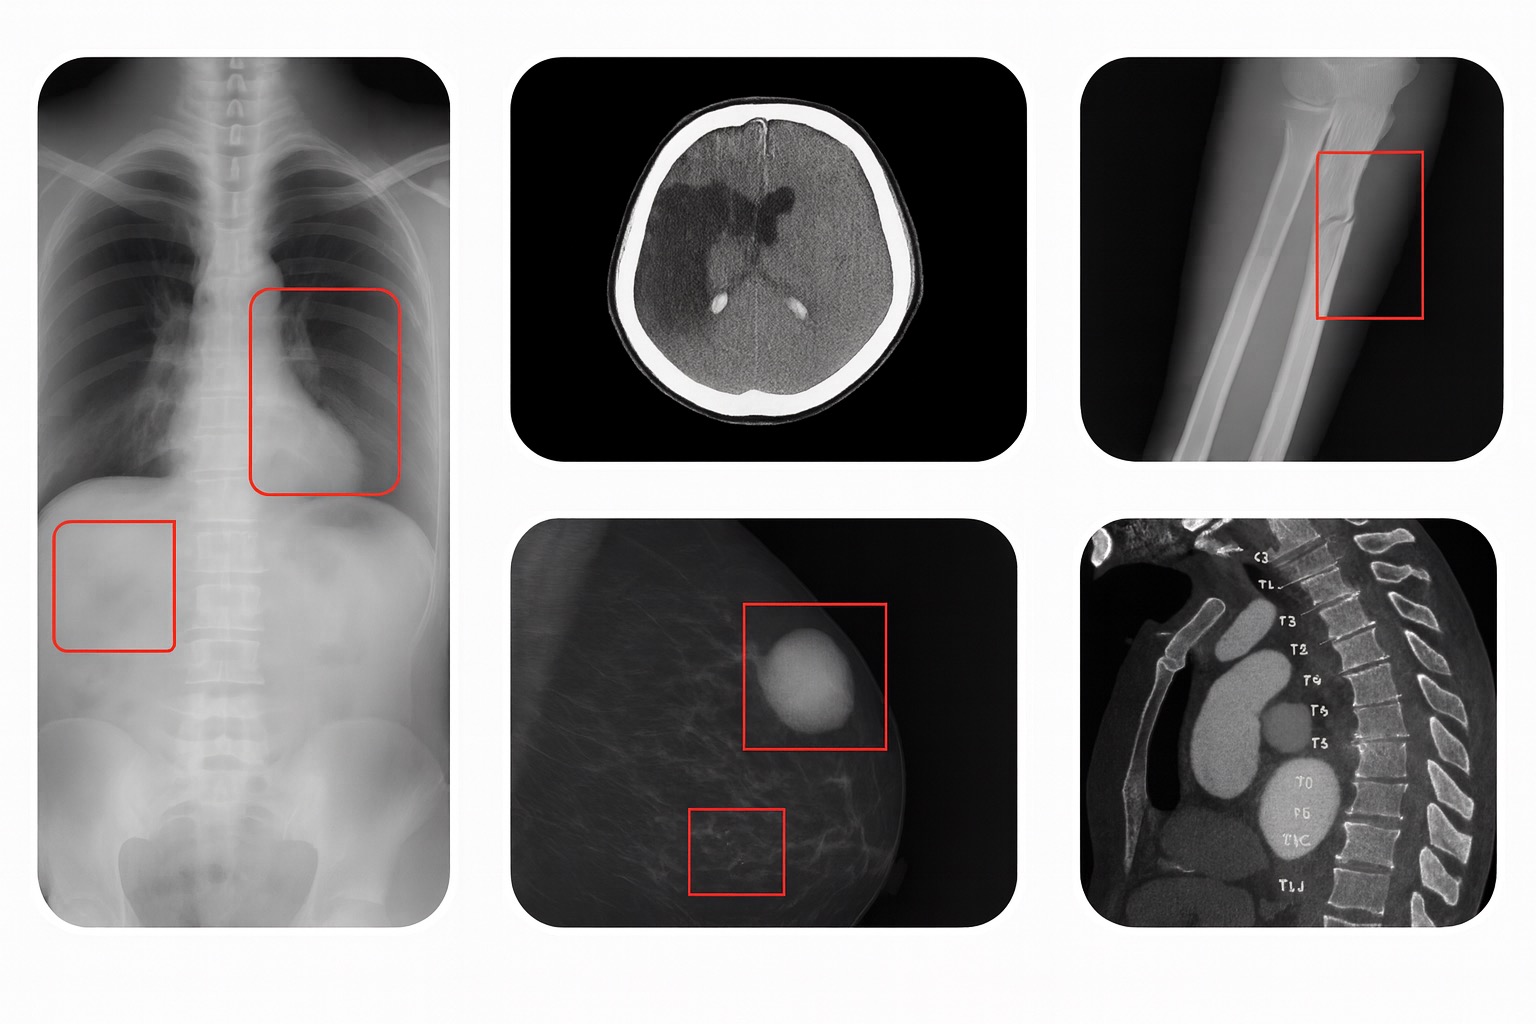

AI in Medical Imaging

When it comes to the adoption of artificial intelligence (AI) in medicine, radiology is leading the charge. The US Food and Drug Administration (FDA) had approved nearly 900 AI/ML enabled devices, and the vast majority of them are in radiology.

At Telerapp, innovation is at the core of our mission to enhance diagnostic accuracy, reduce turnaround times, and improve patient outcomes through cutting-edge AI solutions. Our dedicated R&D team works at the intersection of radiology and machine learning, developing and integrating proprietary and 3rd party algorithms tailored to the most pressing clinical challenges.

Multimodal Imaging

Better Insights in a Single Session: Multimodal imaging with PET/CT and SPECT/CT has become indispensable in clinical practice and in preclinical and basic medical research. Do other combinations of imaging modalities have a similar potential to impact medical science and clinical medicine?

Telerapp’s research and development team is on course to advancing medical imaging technologies by harnessing the power of multimodal imaging technologies, hardware solutions, and software innovations.